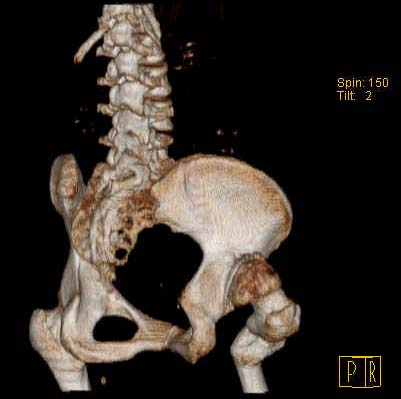

Уважаемые коллеги!Женщина, 35 летВ прошлом по поводу врожденного вывиха бедра перенесла операцию остеотомии по Шанцу

с удлинением правой ноги за счет бедра на уровне диафиза. В последнее время прогрессируют боли в правом тазобедренном суставе, порочное положение правой ноги, затруднена ходьба.Вопросы:1) Целесообразно ли эндопротезирование правого тазобедренного сустава?2) Целесообразный ли следующие действия: канал бедренной кости предполагаем вскрыть для введения ножки протеза на высоте угловой деформации, предполагаем низведение большого вертела с мышцами; протез будет подобран индивидуально, предполагается умеренная версия?В приложении рентгенограммы и трехмерная КТ.В цветном и более качественном варианте КТ размещена здесь

Наше общее мнение - проведение клиновидной остеотомии в зоне дополнительной точки опоры с ее иссечение и укорочением бедра, протезирование ножкой Вагнера.

Похожий случай представляем на ретгенограммах. Операция выполнена в 1996 г.